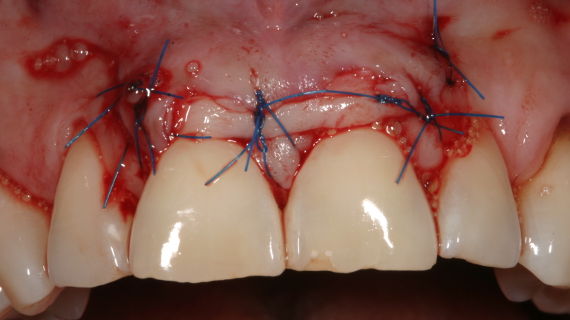

Esta apresentação será focada na definição dos casos de periodontite e na sua abordagem baseada na evidência recente. Toda a apresentação será acompanhada por diversos casos clínicos ilustrativos.